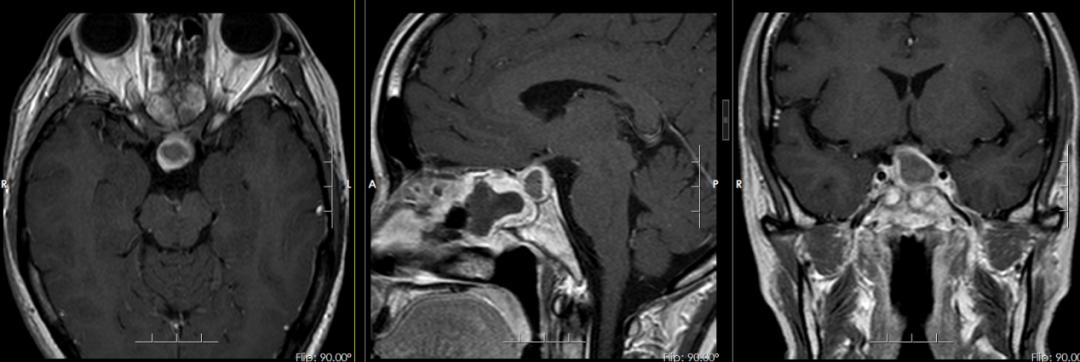

▲术后磁共振

术后复查磁共振提示肿瘤完全切除无残留,性激素检查结果提示泌乳素明显下降。陈娟恢复得也很快,术后住院一段时间后,便顺利出院。